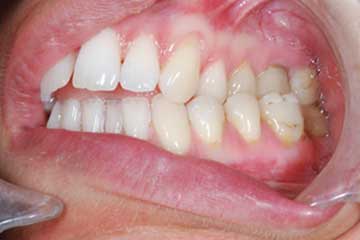

Con protesi fissa superiore e protesi fissa inferiore

sono stati sostituiti da 10 impianti, cioè protesi radicolari endo-ossee che sostengono le protesi fisse superiore ed inferiore.